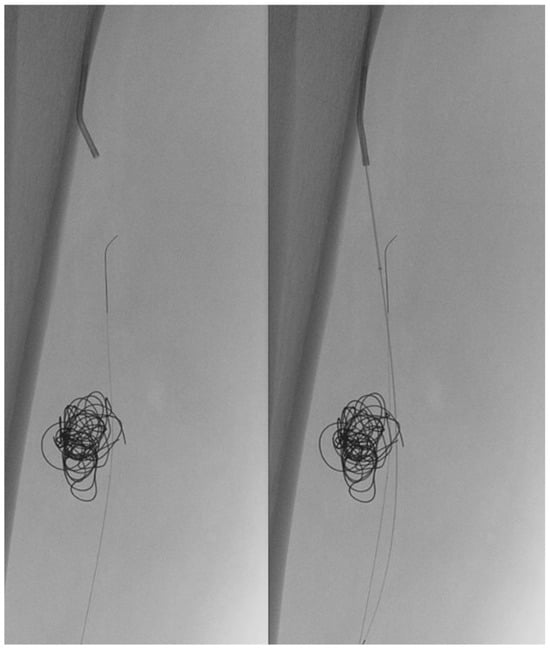

In light of a symptomatic aneurysm, treatment was offered to the patient. After discussing the risks of open and endovascular treatment options with the patient, an endovascular approach was opted for. The presence of a large aneurysm with an AV fistula and venous congestion posed an increased risk of significant bleeding complications associated with open surgery. An antegrade femoral access was obtained via a 5F sheath (Terumo, Shibuya-ku, Tokyo, Japan). After obtaining an angiogram, two coils were deployed in the aneurysm sac (Concerto PGLA helical PV-20-50-Helix and Concerto PGLA 3D PV-18-40-3D, Medtronic, Minneapolis, MN, USA), with the aim of causing sac thrombosis and obliterating the flows from multiple AV fistulas. As anticipated, this did not lead to complete occlusion of the aneurysm and AV fistula. A retrograde pedal access was obtained, and cannulation of the PTA was successfully performed with a V14 guidewire (Boston Scientific, Marlborough, MA, USA) (Figure 2 and Figure 3). After obtaining guidewire access, the aneurysm was excluded with a stent graft (Viabahn Endoprosthesis 5 mm × 50 mm, WL Gore, Flagstaff, AZ, USA). Immediately after the procedure, angiography control visualized complete exclusion of the pseudoaneurysm, occlusion of the sac, and absence of any AVF (Figure 4). Postoperatively, the patient reported pain reduction. Both pedal pulses were palpable. Postoperative antithrombotic therapy included aspirin 100 mg and clopidogrel 75 mg daily for 6 months. Additionally, Class 2 compression stockings were recommended for 1 month. After 18 months of follow-up, the patient was free of symptoms, and the stent graft was patent.

Figure 3.

(Left) to (right). Retrograde pedal access was obtained and cannulation was successful with a V14 Guidewire.